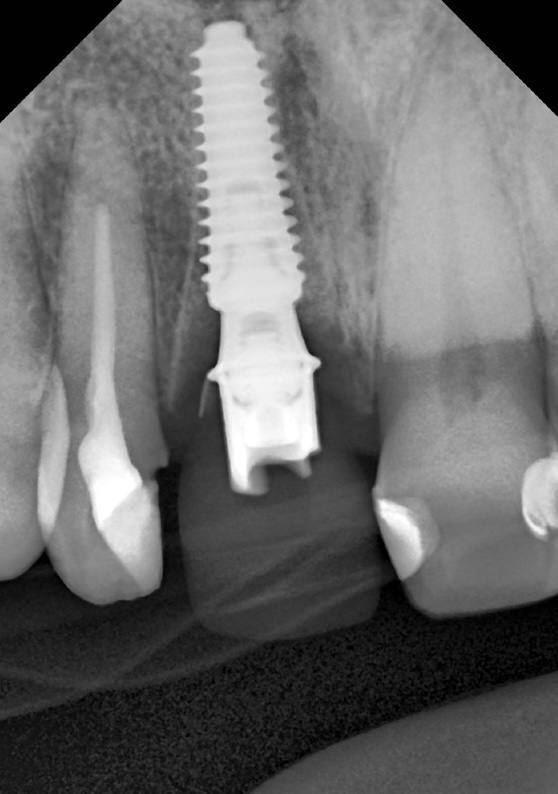

Одномоментная имплантация 1.1

AnyRidge, мультиюнит Octa, CCT, временная коронка